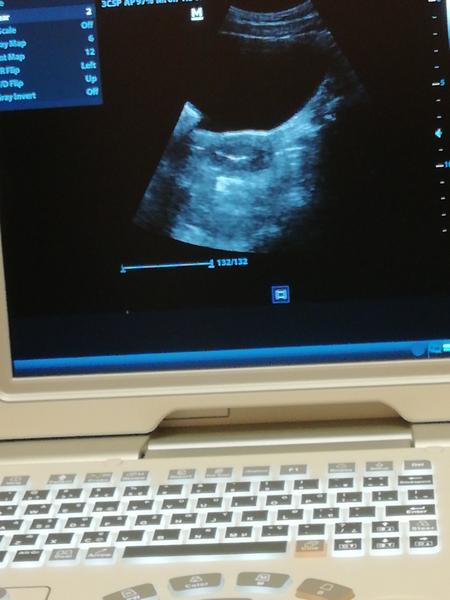

@nikusik0107 Áno, na monitore. Potom aj maternicu a v tom emryjko. To biele v strede je tekutina a v tom embryjko 😉